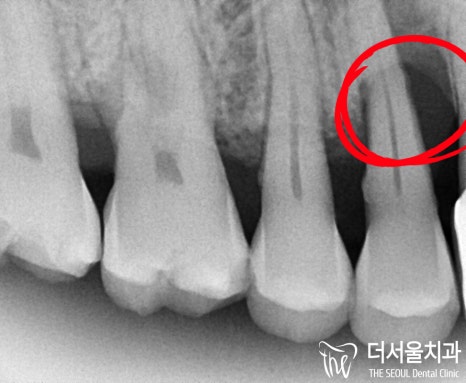

# 14, # 26 소구치 및 대구치에

치주염으로 인한 골소실이

나타난 것을 볼 수 있었습니다.

시커멓게 변해버린 곳이

이미 염증이 나타났었으며,

골소실이 일어난 것이죠.